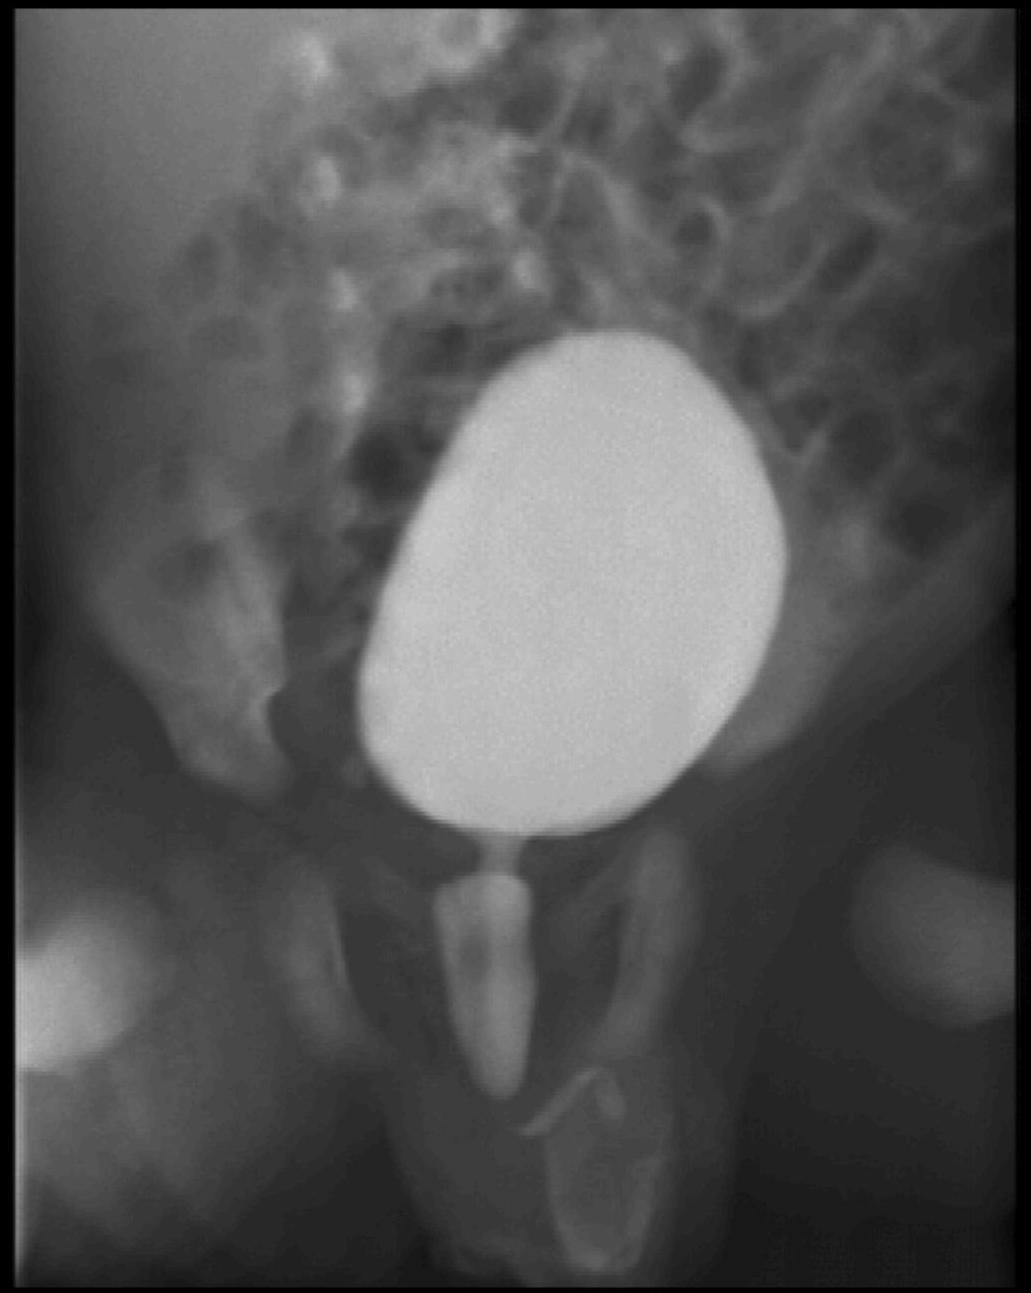

Image

22.The calices and the pyelon of the kidney are markedly dilated, the parenchyma is thinner. Severe hydronephrosis. The ureter is not visible. Pyelouretral stenosis.

23. Miction cystourethrography. A small diverticula is seen on the right side, the proximal urethra is dilated, beneath is a filling defect. Subvesical obstruction, dorsal urethral valve.